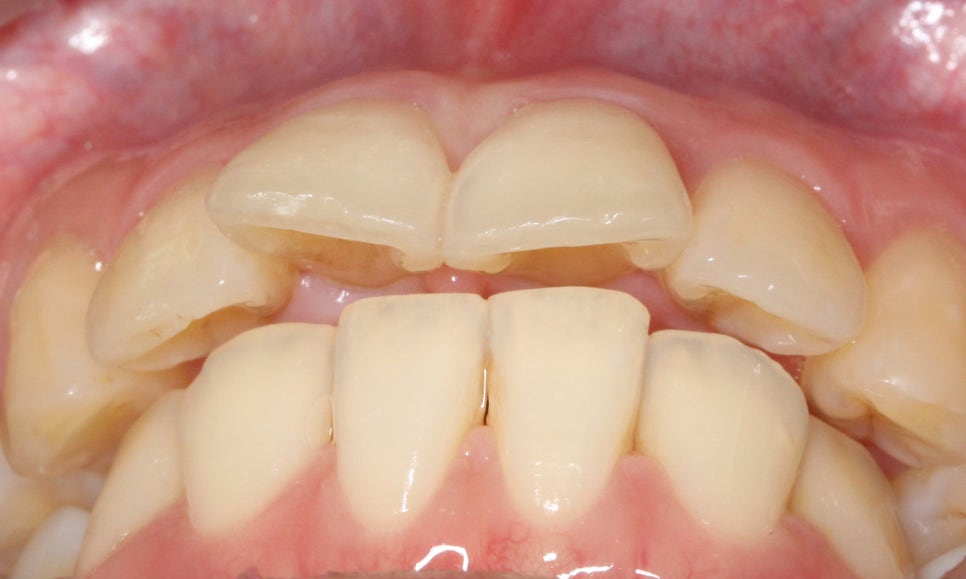

전치부의 돌출감을 아래에서 살펴보면

상악의 입툭튀 정도를 가늠할 수 있는데요,

대치동치과에서는 이러한 돌출입 Case를

효과적으로 교정하기 위해

다양한 치아교정 방법과

브라켓을 적용하고 있습니다.

이어서 Overjet사진을 보시면

상악과 하악의 돌출감 차이를

확인할 수 있는데요,

상악의 성장이 과도할 경우

위처럼 윗니가 과도하게

전방으로 튀어나오는 증상이 나타나거나

혹은 턱의 길이가 짧고 무턱증상을 보일 수 있습니다.